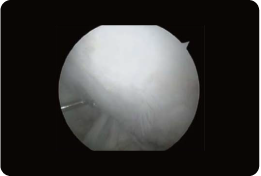

図のとおり、関節鏡手術で、左の大腿骨の荷重がかからないところ2箇所から0.4gの健常な軟骨を採取。